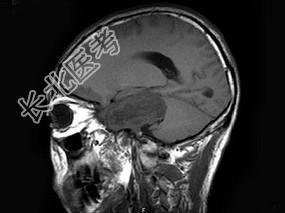

- 单项选择题男,38岁, 左侧面部麻木半年,头颅MRI见颅内占位性病变, 最可能的诊断为 ( )

B、三叉神经瘤